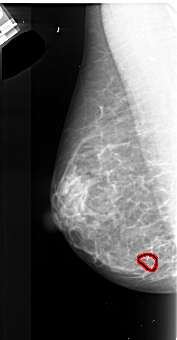

A_1022_1.RIGHT_MLO

LEFT_MLO LINES 4756 PIXELS_PER_LINE 2476 BITS_PER_PIXEL 16 RESOLUTION 42 OVERLAY

FILE: A_1022_1.LEFT_MLO.OVERLAY

TOTAL_ABNORMALITIES 1

ABNORMALITY 1

LESION_TYPE CALCIFICATION TYPE PLEOMORPHIC DISTRIBUTION CLUSTERED

ASSESSMENT 4

SUBTLETY 3

PATHOLOGY MALIGNANT

TOTAL_OUTLINES 1

BOUNDARY